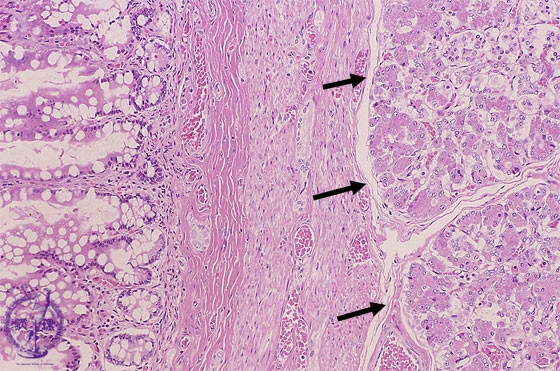

Microscopic view, high power; The inner lining is covered by mucosa resembling that of the small intestine with pancreatic tissue is present in the wall (arrow)

Click the image to see the enlarged image.